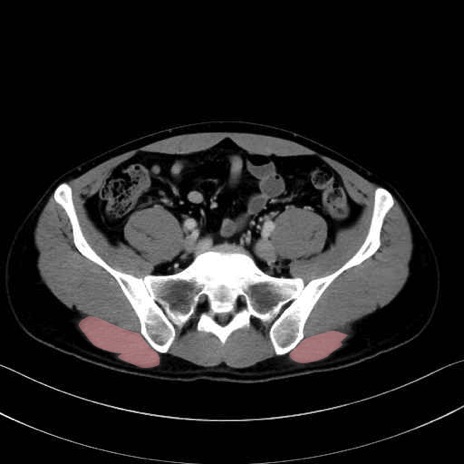

大殿筋 (Gluteus maximus)